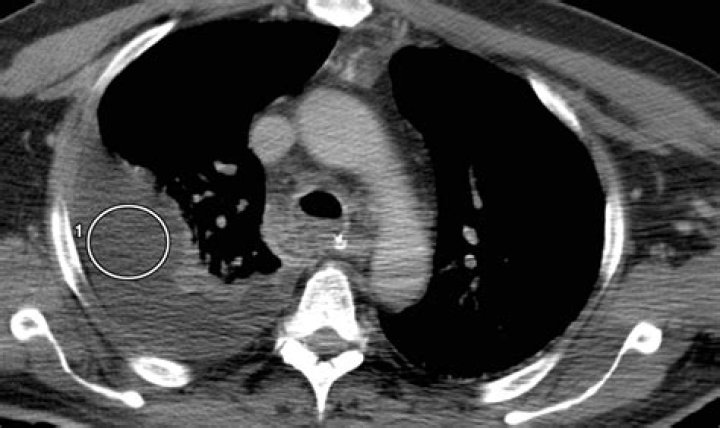

Chylothorax is a rare but serious condition in which lymph formed in the digestive system (chyle) accumulates in your chest cavity.

What is chylothorax? Chylothorax is a rare condition in which lymphatic fluid leaks into the space between the lung and chest wall. When this fluid builds up in the lungs, it can cause a severe cough, chest pain and difficulty breathing. Chylothorax is a lymphatic flow disorder.

A chylothorax (ky-low-thor-ax) is the buildup of chyle (kile), a milky white fluid, in the space around the lungs. This makes it difficult to breathe. Chyle is a normal fluid produced in the bowel when we digest food. It is milky-colored when fatty food or drink is digested.

Thoracentesis and pleural fluid analysis are the criterion standards to establish a diagnosis of chylothorax. Alternatively, in a postsurgical patient, tube thoracostomy output can be analyzed. Pleural fluid analysis for triglyceride content helps to confirm the diagnosis of chylothorax.

Chylothorax is a rare condition that results from thoracic duct damage with chyle leakage from the lymphatic system into the pleural space, usually on the right side. It has multiple aetiologies and is usually discovered after it manifests itself as a pleural effusion.